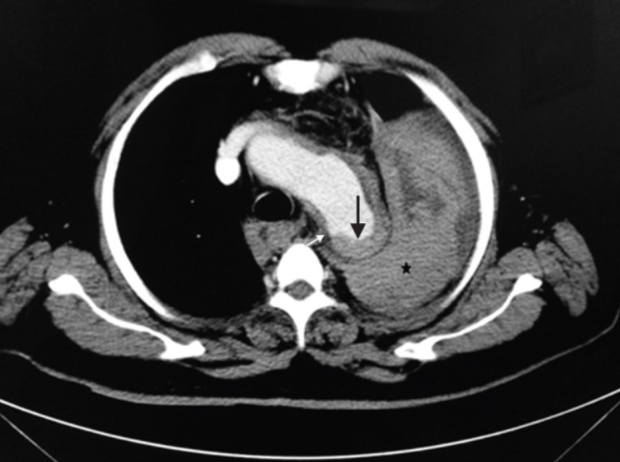

Bác sĩ Nguyễn Minh Đức – Giảng viên Trường Đại học Y Phạm Ngọc Thạch (TPHCM), trước đó, bệnh nhân đến bệnh viện khám do có các triệu chứng của rối loạn tiêu hóa. Tuy nhiên, trong quá trình khám bệnh, bác sĩ đã phát hiện bệnh nhân bị phình động mạch chủ ngực, kích thước lên tới 50mm.

Bác sĩ tư vấn bệnh nhân can thiệp điều trị đặt stent graft ngay vì có nguy cơ vỡ túi phình động mạch chủ ngực nhưng bệnh nhân mong muốn là quay trở lại Úc điều trị. Dù được bác sĩ giải thích về những nguy cơ có thể xảy ra vỡ túi phình, thậm chí có thể nguy kịch tới tính mạng nhưng bệnh nhân vẫn nhất quyết từ chối điều trị và đặt vé máy bay về Úc.

Tuy nhiên, chưa kịp bay thì ngay hôm sau, bệnh nhân đã phải nhập viện cấp cứu trong tình trạng hôn mê. Theo người nhà, người bệnh đã bất tỉnh sau một cú hắt xì. Qua kết quả chụp CT, bác sĩ xác định bệnh nhân bị vỡ túi phình, khiến người bệnh sốc và tử vong ngay sau đó.